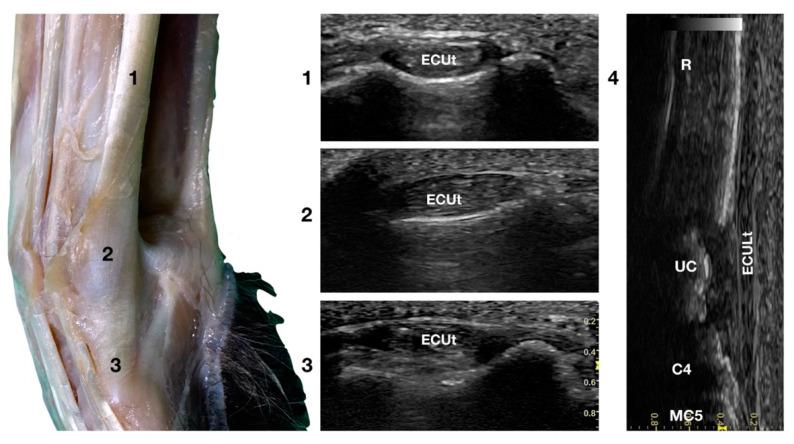

Recent literature has demonstrated that high-resolution ultrasonographic anatomy of the canine carpus is possible; however, only the structures of the dorsal face were described. The aims of this prospective study were: (1) to describe the normal ultrasonographic appearance of the carpal tendons in sporting Border Collies; (2) to measure the height, length, and thickness of the tendon at the radial ulnar notch level in order to create a baseline reference for the breed, and (3) to describe a standardised protocol to ultrasonographically evaluate the carpal faces and visible tendinous structures. A pilot study based on ten cadaveric front limbs was used to identify the structures. A subsequent clinical phase of the study using twenty-six Border Collies was recorded. The tendons of the Extensor Carpi Radialis, Extensor Digitorum Communis, and Extensor Digitorum Lateralis were identified and followed from the tenomuscular junction to the distal insertion on the dorsal face of the digits. On the lateral face, the tendon of the Extensor Carpi Ulnaris was recognised and followed. On the palmar face, the two heads of the Flexor Carpi Ulnaris tendon ending on the accessory carpal bone, the adjacent Flexor Digitorum Superficialis tendon, and the deep and medially located Flexor Digitorum Profundus tendon were seen and followed. The Flexor Carpi Radialis and the Abductor Pollicis Longus tendons were seen in the medial carpal face. The ulnar notch of the radius was used as the measurement and starting point of the ultrasonography. These data could be used as a standard reference in the case of chronic overuse and trauma-induced changes in the canine carpus.

近期文献表明,对犬腕关节进行高分辨率超声解剖是可行的;然而,此前仅描述了其背侧的结构。本前瞻性研究的目的是:(1)描述运动型边境牧羊犬腕部肌腱的正常超声表现;(2)测量桡尺切迹水平处肌腱的高度、长度和厚度,以便为该品种建立基线参考;(3)描述一种标准化方案,用于超声评估腕关节面和可见的肌腱结构。基于十具尸体前肢进行了一项初步研究以识别相关结构。随后记录了使用二十六只边境牧羊犬的临床研究阶段。确定了桡侧腕伸肌、指总伸肌和指外侧伸肌的肌腱,并追踪其从肌腱-肌肉连接处至手指背侧的远端附着点。在外侧,识别并追踪了尺侧腕伸肌的肌腱。在掌侧,可见止于副腕骨的尺侧腕屈肌肌腱的两个头、相邻的指浅屈肌肌腱以及位于深部和内侧的指深屈肌肌腱,并进行了追踪。在腕关节内侧可见桡侧腕屈肌和拇长展肌肌腱。桡骨的尺切迹被用作超声测量的起点和起始点。这些数据可作为犬腕关节慢性过度使用和创伤性改变情况下的标准参考。